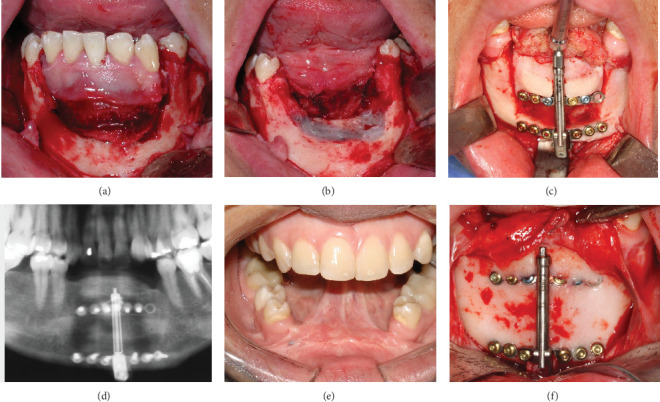

目的:本病例报告详细介绍了一名28岁女性前下颌弓复发性中央巨细胞肉芽肿(CGCG)的长期治疗。病例报告:在2007年首次手术切除后,导致明显的骨缺损,采用多学科方法恢复下颌完整性和功能。2009年,使用DePuy Synthes牙槽牵张器进行牙槽牵张成骨。随后,在2011年进行了自体上牙体植骨,以优化牙槽嵴轮廓。2012年放置了4个Neodent CM植入物,随后进行了假肢康复。2024年的15年随访显示了良好的结果,种植体周围组织稳定,骨水平维持正常,假体功能齐全。本病例强调了包括牵张成骨和自体植骨在内的先进手术技术在治疗复杂CGCG病例中的疗效。结果和结论:成功的长期结果强调了综合治疗方法和定期随访对解决侵袭性和复发性cgcg带来的挑战的重要性。本报告提供了有价值的见解,在广泛的CGCG治疗后,全面功能和美学修复的潜力,强调了在颌面重建中良好协调的多学科方法的好处。

Aim: This case report details the long-term management of a recurrent central giant cell granuloma (CGCG) in the anterior mandibular arch of a 28-year-old female. Case Report: Following initial surgical resection in 2007, which resulted in a significant bony defect, a multidisciplinary approach was employed to restore mandibular integrity and function. In 2009, alveolar distraction osteogenesis was performed using a DePuy Synthes alveolar distractor. Subsequently, in 2011, autogenous onlay bone grafting was carried out to optimize the alveolar ridge contour. Four Neodent CM implants were placed in 2012, followed by prosthetic rehabilitation. The 15-year follow-up in 2024 revealed excellent outcomes, with stable peri-implant tissues, maintained bone levels, and a fully functional prosthesis. This case highlights the efficacy of combining advanced surgical techniques, including distraction osteogenesis and autogenous bone grafting, in managing complex CGCG cases. Results and Conclusion: The successful long-term outcome underscores the importance of a comprehensive treatment approach and regular follow-up in addressing the challenges posed by aggressive and recurrent CGCGs. This report provides valuable insights into the potential for fully functional and aesthetic restoration following extensive CGCG treatment, emphasizing the benefits of a well-coordinated, multidisciplinary approach in maxillofacial reconstruction.